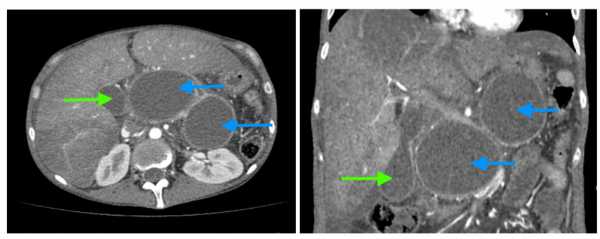

Как выглядят кисты поджелудочной железы? На компьютерных томограммах (КТ) у молодой женщины, злоупотребляющей алкоголем, с множественными эпизодами острого панкреатита в анамнезе, видны две большие псевдокисты (синие стрелки) головки, тела и хвоста поджелудочной железы, сдавливающие на окружающие ткани. Желчный пузырь (зеленая стрелка) увеличен из-за сдавления пузырного протока псевдокистой. Обратите также внимание на признаки алкогольного гепатита: увеличение печени и неравномерное накопление ею контраста, жидкость вблизи ее края.